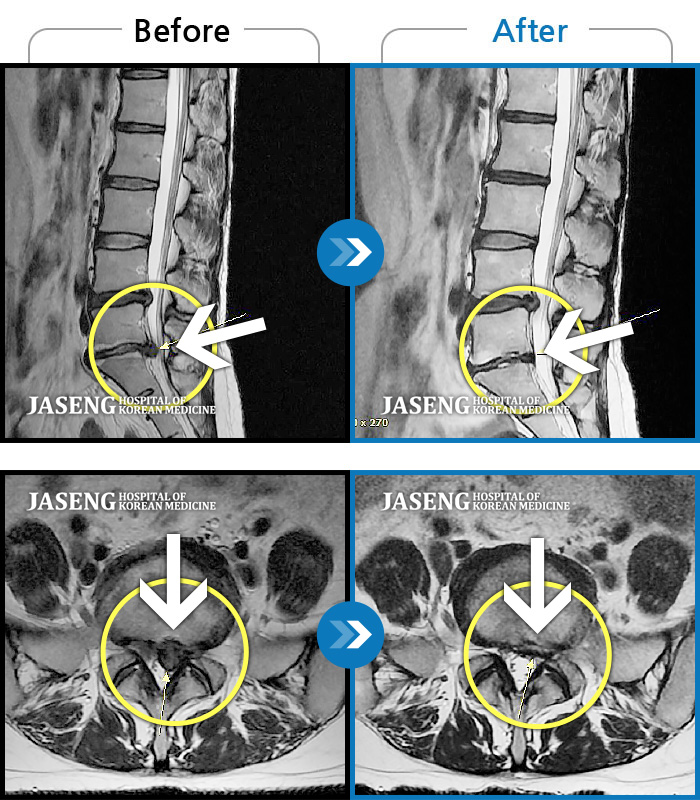

ȯںп Ǹ ǿ ԿǾ, ο ġ ۿ Ƿ ġḦ Ͻñ ٶϴ.